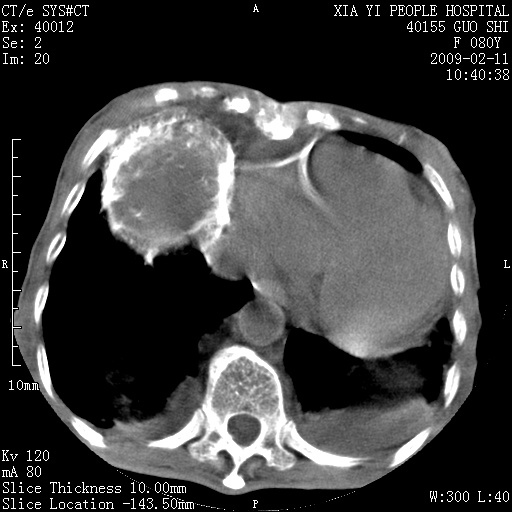

以下是引用随光逐影在2009-2-16 16:34:00的发言:[br]1)考虑右前纵隔皮样囊肿。2)双侧少量胸腔积液。

以下是引用zjzjr在2009-2-16 17:30:00的发言:[br]支持囊性畸胎瘤 双侧少量胸腔积液。